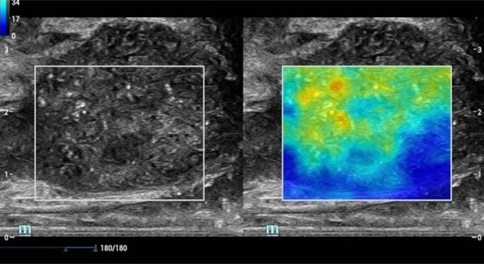

ElastografĂa de prĂłstata cualitativa por compresiĂłn y shear wave para dos mĂ©todos de biopsia diferentes.

ElastografĂa de prĂłstata: Carcinoma de prĂłstata

La nueva ElastografĂa Sound Touch (STE) permite tener una velocidad de cuadros mĂĄs alta en el campo, hasta 10 veces mĂĄs rĂĄpida que antes*, lo que brinda mĂĄs confianza en el diagnĂłstico clĂnico.

STE normal

STE de alta velocidad de cuadros